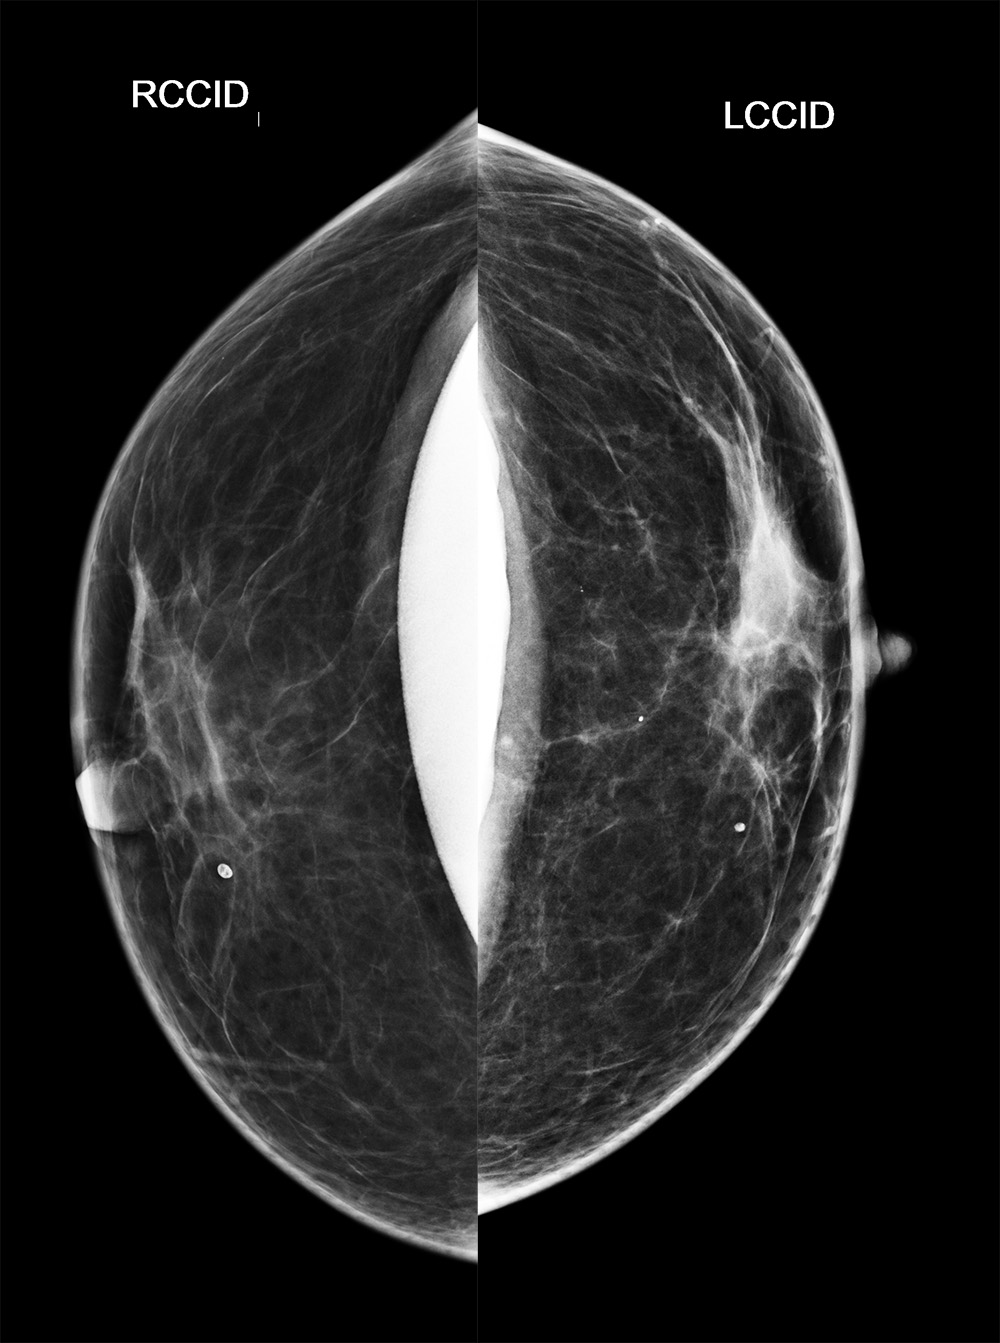

◂Breast Anatomy